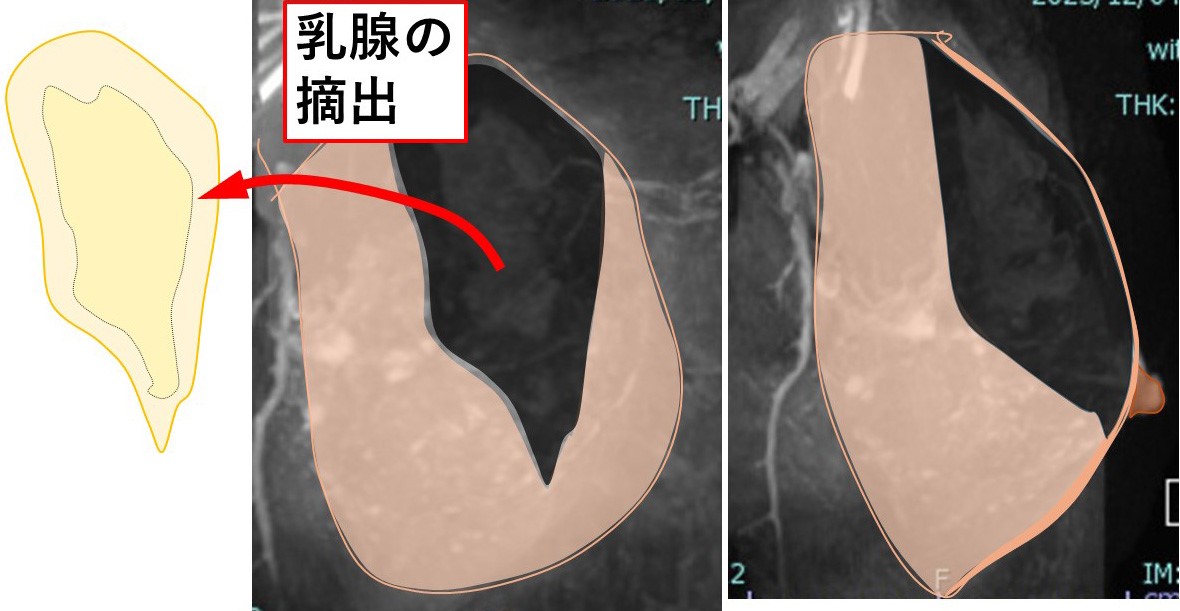

5. 癌の(マージンをつけての)摘出

6. 乳腺の(欠損部の)縫合

乳腺の端と端を縫合します。

7. 乳腺の縫合閉鎖

結構大きい欠損なのに、乳腺がそんなに(縫合できるほど)伸びるのか??

8. それには訳があります。

乳腺は「厚み」があるので、それを「薄く引き伸ばす」イメージです。